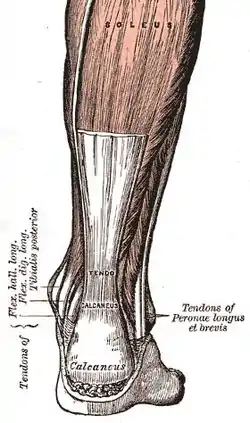

| Achilles tendon (a commonly affected tendon) | |

Tendinopathy is a type of tendon disorder that results in pain, swelling, and impaired function.[3][1] The pain is typically worse with movement.[6] It most commonly occurs around the shoulder (rotator cuff tendinitis, biceps tendinitis), elbow (tennis elbow, golfer's elbow), wrist, hip, knee (jumper's knee, popliteus tendinopathy), or ankle (Achilles tendinitis).[3][7][2]